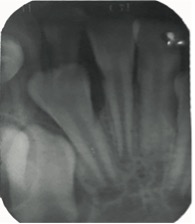

En el examen clínico intraoral, se observó dentición mixta, todos los dientes limpios, sin embargo, con maloclusión, por esa razón el paciente fue referido para evaluación y tratamiento ortopédico. Conforme la mamá había reportado, los incisivos laterales primarios inferiores estaban en oclusión (Figura 1) y sin movilidad. A través de la radiografía periapical en la región de los incisivos laterales inferiores (Figuras 2 y 3), fue observado que los gérmenes de los incisivos laterales inferiores permanentes se encontraban en la etapa 8 de Nolla, entonces, deberían estar estallando en la cavidad oral.

Figura 2: Radiografía periapical del diente 82.

Figura 3: Radiografía periapical del diente 72.